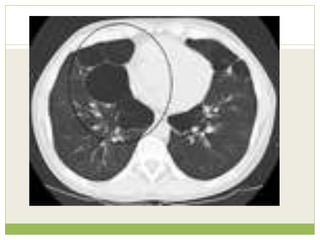

• #58ย A lateral chest x-ray of a person with emphysema. Note the barrel chest and flat diaphragm.